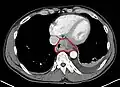

Esophageal cancer as shown by a filling defect during an upper GI series